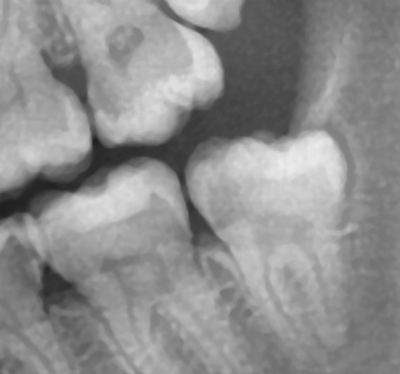

А для того, что ортопантомография (ОПТГ, обзорный или панорамный снимок зубов), является плоскостным, а значит происходит наложение каждой детали снимка послойно друг на друга. Следовательно, рассмотреть объект исследования, в частности, область зуба мудрости, расположенного рядом нижнечелюстного нерва, во всех плоскостях, под иным углом или другой проекции невозможно. КЛКТ (Конусно-лучевая компьютерная томография), напротив дает нам такую возможность.